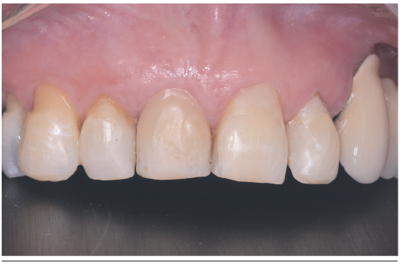

De acuerdo a lo presentado en este caso clínico mediante un colgajo desplazado lateral e injerto de tejido conectivo subepitelial fue posible lograr una cobertura total de una recesión gingival de gran longitud RT1 de Cairo11 en un diente 1.1.